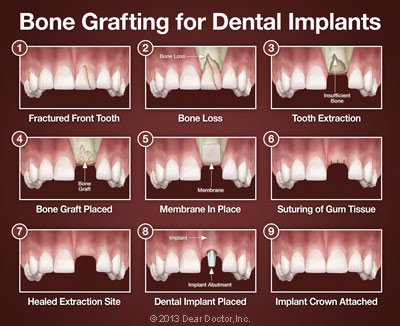

Tooth Extractions — These days, it is very common to deposit bone grafting material into a tooth socket after a tooth has been removed. That way, should you want to replace your tooth with a dental implant later on, that option will be available.

Dental Implants — In this optimal tooth-replacement system, a small titanium post embedded in the jawbone is attached to a highly realistic dental crown, permanently replacing the missing tooth. Implants require good bone volume and density to achieve their excellent functionality and high success rates. If you have already experienced bone loss, a graft can help regenerate enough bone to place the implant successfully.